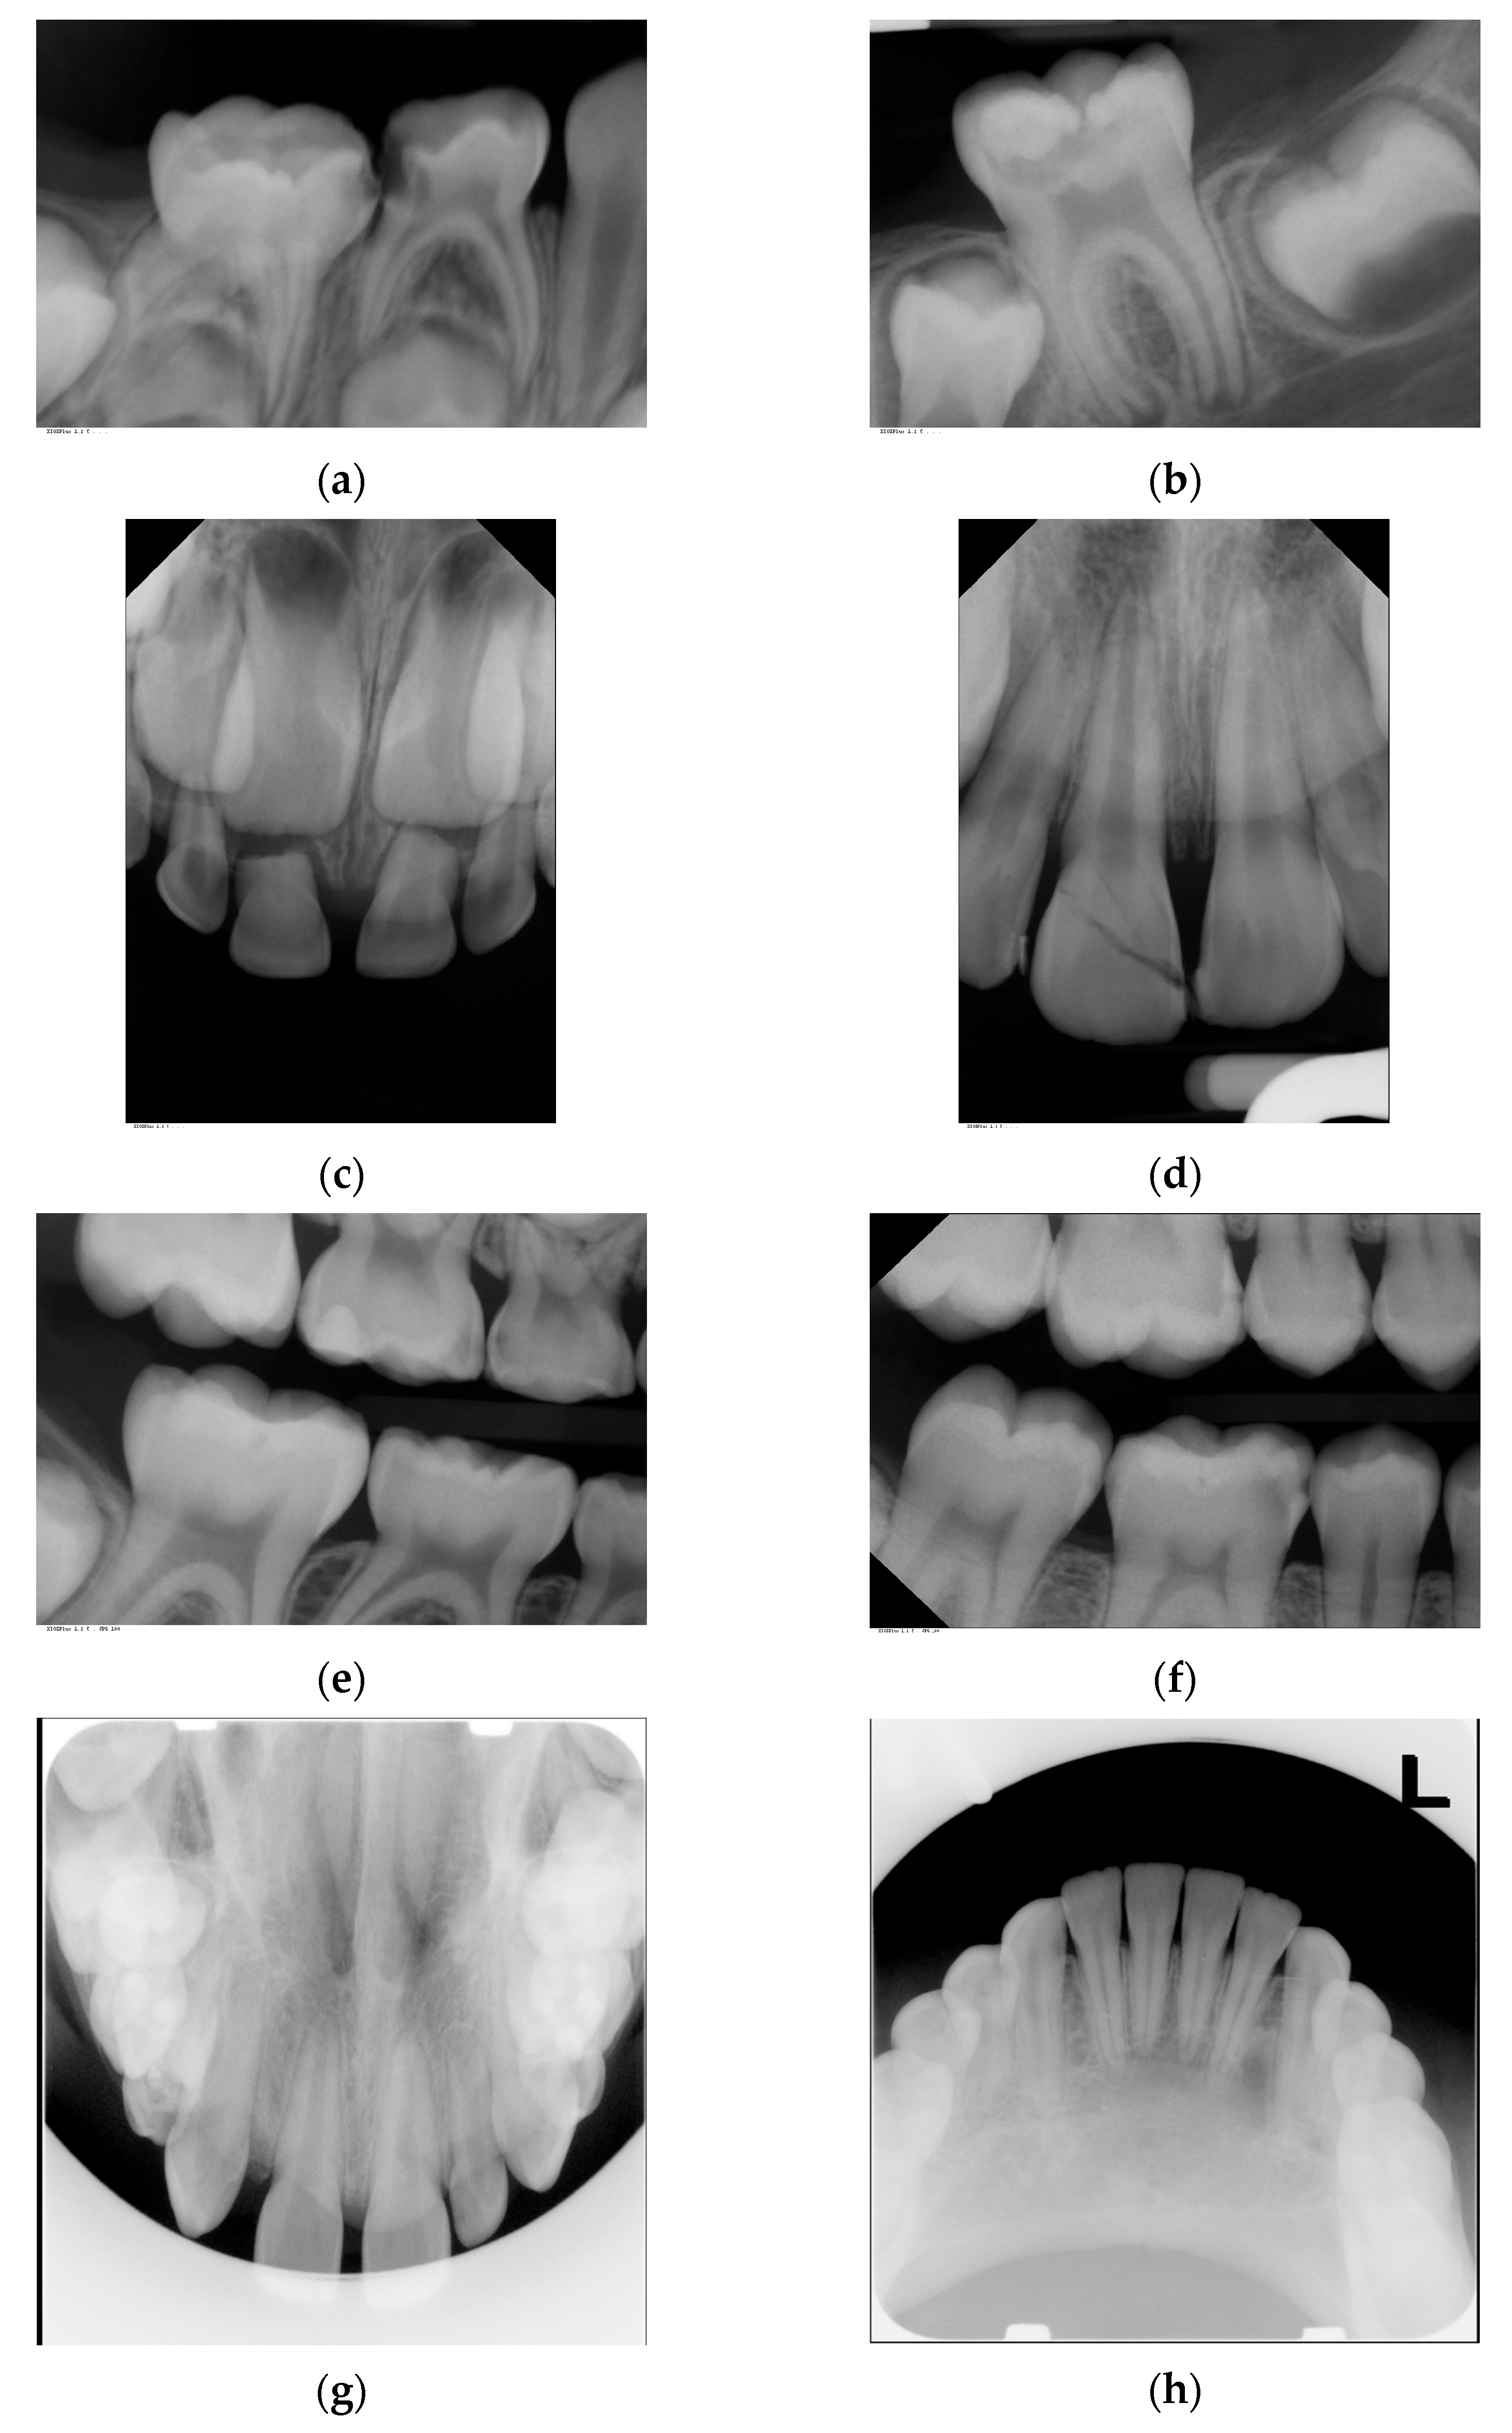

The present evaluation was based on a total number of 4455 intraoral radiographs taken in 2195 patients. In total, 3128 dental, 903 bitewing and 424 occlusal X-rays were included. Examples of the intraoral X-ray images are shown in Figure 1.

Figure 1.

Examples of investigated intraoral radiographs: (a) dental radiograph of primary molars for caries and apical diagnostics; (b) dental radiograph of permanent molar for caries progression and apical diagnostics; (c) dental radiograph of primary teeth for trauma diagnostics; (d) dental radiograph of permanent teeth for trauma diagnostics; (e) bitewing radiograph for caries detection in primary molars; (f) bitewing radiographs for caries diagnostics in permanent molars; (g) occlusal radiograph for diagnosis of tooth germ position in the upper jaw; (h) occlusal radiograph for diagnosis of pathology in the lower jaw.